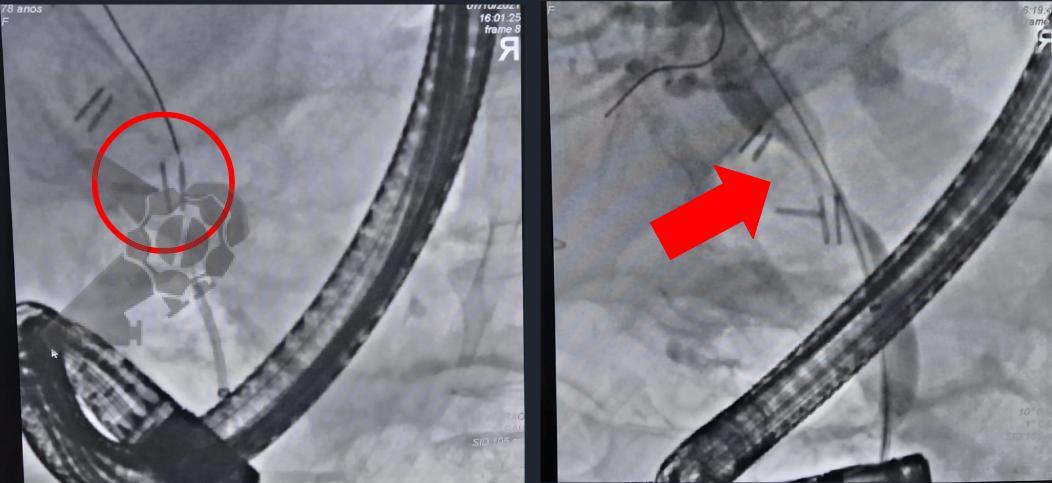

L.R.S., masculino, 8 meses, nascido a termo, com diagnóstico pré-natal de atresia de esôfago com fístula traqueoesofágica distal (Vogt IIIb/Gross C), submetido à correção cirúrgica no 3º dia de vida. Aos 3 meses, passou a apresentar episódios recorrentes de tosse durante a alimentação, engasgos, regurgitação e perda de peso progressiva. A mãe relatou dificuldade em introduzir alimentos sólidos e episódios recorrentes de infecção respiratória nos últimos dois meses. Solicitada endoscopia digestiva alta, que evidenciou estenose puntiforme da anastomose esofágica. Iniciada terapia endoscópica com dilatação esofágica utilizando vela de Savary-Gilliard. Foram realizadas 4 sessões com intervalo de 2 semanas, com melhora progressiva da aceitação alimentar e ganho ponderal adequado. Após a 4ª dilatação, o paciente encontra-se em boa evolução clínica, com alimentação por via oral plena, sem episódios de engasgos ou perda ponderal.

O tratamento inicial a ser considerado é a dilatação endoscópica, seja com o balão hidrostático ou com a vela de Savary – Gilliard, não havendo diferença nos desfechos, de acordo com a literatura atual, entre as duas técnicas [12]. Entretanto, alguns trabalhos sugerem que a dilatação com balão pode apresentar menor risco de complicações[12,13,14]. Estudos mostram uma média de três sessões de dilatação para a resolução do quadro, sendo estas intervaladas em um período de duas a quatro semanas, a depender da sintomatologia e evolução clínica do paciente, sendo o ganho ponderal um dos fatores clínicos mais importantes a serem considerados [8,13].